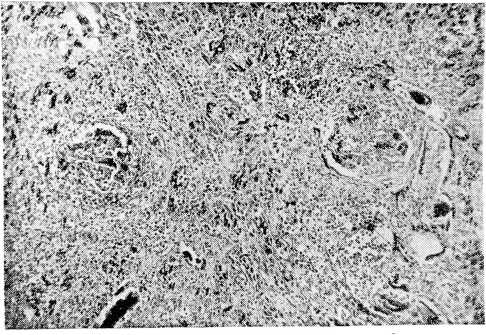

Рис. 2. Гломерулонефрит при болезни Шенлейн — Геноха

Микроскопическое исследование. Почка: клубочки увеличены в объеме, почти полностью выполняют просвет капсул. Пролиферация эндотелия сосудистых петель клубочков, накопление лейкоцитов в просвете сосудов. Резкое полнокровие клубочков, стазы и кровоизлияния с выходом эритроцитов в просвет капсул.. Фибриноидный некроз отдельных сосудистых петель клубочков. Зернистая дистрофия эпителия канальцев. В просветах канальцев скопления эритроцитов. Стенка к и ш- к и: обширные кровоизлияния во всех слоях стенки, отек подслизистого слоя. Небольшие изъязвления в слизистой оболочке, дно которых пропитано кровью. Пролиферация эндотелиальных и адвентициальных элементов стенки мелких артерий, инфильтрация стенки лейкоцитами, среди которых довольно много эозинофилов, образующих адвентициальные клеточные муфты. Пролиферирующий эндотелий капилляров местами почти целиком выполняет их просвет. Кожа: множественные геморрагии в дерме и в подкожной клетчатке. Набухание и выраженная пролиферация эндотелия капилляров и мелких сосудов с почти полным закрытием их просвета. Местами границы сосудов стерты. Периваскулярные клеточные муфты. В просвете мелких артерий и вен встречаются тромбы. Некроз стенки сосудов.

Микроскопическое исследование. Почка — большая часть клубочков увеличена в размерах за счет пролиферации эндотелия и накопления лейкоцитов в просветах сосудистых петель; увеличенные клубочки почти целиком выполняют просветы капсул. Некроз части сосудистых петель. Отдельные клубочки деформированы, имеют лопастную форму, бедны клеточными элементами и частично фиброти- зированы. Отмечается очаговое утолщение капсулы клубочков и образование полулуний. Дистрофия эпителия мочевых канальцев, в просвете их цилиндры и кровь. Набухание и фибриноидный некроз стенки мелких артерий и артериол почки, пролиферация эндотелия. Местами разрастание межуточной соединительной ткани. В интерсти- ции почки видны круглоклеточные и лейкоцитарные инфильтраты, расположенные преимущественно вокруг клубочков и мелких артерий. Местами лейкоциты инфильтрируют стенки мелких артерий, образуя вокруг последних значительные муфты. Сердце: Деструкция стенки мелких артерий и артериол миокарда с разволокнением и набуханием, а местами и фибриноидным некрозом, пролиферацией эндотелия и образованием небольших адвентициальных клеточных муфт. Селезенка: множественные мелкие очажки некроза в пульпе, редукция фолликулов, местами картины эндопериваскулита. Стенка пищевода: небольшие язвы слизистой оболочки. В подслизистом слое и в ад- вентиции пищевода мелкие артерии в состоянии фибриноидного некроза, а местами и полной деструкции с широкими эозинофильными муфтами вокруг них. Резкое умень- щение просвета и утолщение стенки некоторых сосудов, встречаются тромбы в различной стадии организации. Стенка кишки: обширные кровоизлияния в подслизистом и мышечном слоях, местами пропитывание кровью всей стенки, пролиферация эндотелия капилляров с почти полным стиранием их просвета. Пролиферация эндотелиальных клеток и адвентициальных элементов стенки мелких артерий и вен. Встречаются периваскулярные лейкоцитарные инфильтраты.